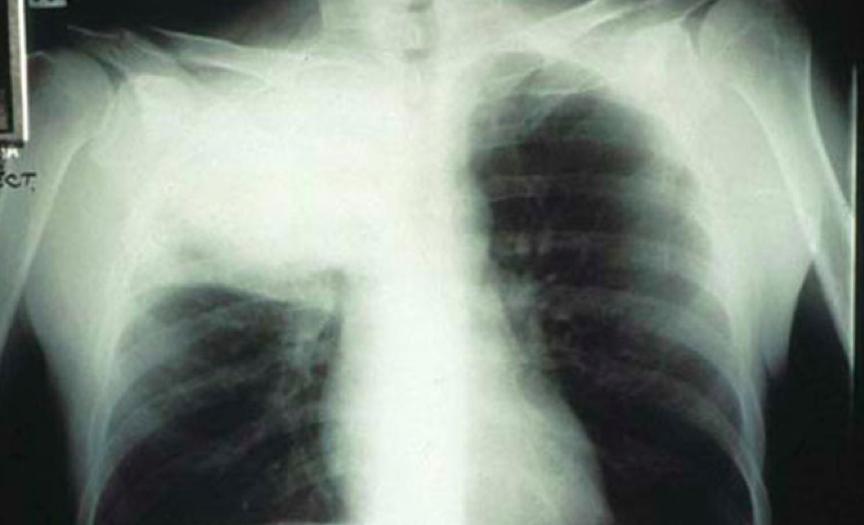

对有免疫缺陷的人来说,新型隐球菌肺炎年发病率高达6%到10%[5][6]。这些人里,症状稍轻的人会开始咳嗽,而严重的情况下,则会发烧、缺氧、呼吸急促,好在一般不会要命。

被新型隐球菌感染的肺部X光片丨doctorfungus.org